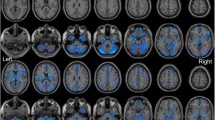

We found significant decreases of cortical thickness in left orbitofrontal and inferior frontal (extending to precentral) regions in the TN group compared to the HCs (p < 0.05, FWE corrected; Fig. 1, Table 2). Figure 1 shows the location of these clusters on the cortical surface, and Table 2 lists the detailed information.

We found a significant decrease of gyrification in the left superior frontal gyrus in the TN patients (Fig. 1, Table 2).

We found significant decreases of sulcal depth in the bilateral superior frontal and anterior cingulate regions in the TN patients compared to the HCs.

In this study, a CAT12-based cortical morphometry was used to quantify changes in cortical thickness, gyrification index, and sulcal depth in the patients with trigeminal neuralgia. We found that the morphological changes of cortex were mainly located in the prefrontal cortex and anterior cingulate region (Fig. 1). In addition, we found negative correlations between mean cortical thickness/gyrification index and pain intensity.

We found that, compared to the control group, the cortical characteristics of TN patients, including decreased cortical thickness, gyrification index, and sulcal depth, were mainly located in the frontal region (Fig. 1 and Table 2). The superior frontal gyrus (extending to the anterior cingulate cortex), inferior frontal gyrus and orbitofrontal cortex belong to the prefrontal cortex, which plays an important role in emotion, cognitive processing and pain management31,32,33. FMRI studies have shown that mood and pain management abnormalities caused by chronic pain are associated with changes in prefrontal-cingulate neural network activation5,34,35,36. For example, Rottmann et al.34 evaluated the effect of low-frequency electrical stimulation and found brain activation in the insula, anterior cingulate cortex, superior temporal gyrus, and prefrontal cortex. A recent meta-analysis concluded that the major regions associated with structural and functional changes in TN include the frontal and cingulate cortex5. Brain morphological studies have also found abnormal structural changes in the frontal lobe and cingulate regions of pain patients37,38,39. For example, using VBM, Apkarian et al.37 found for the first time that gray matter density decreased in the bilateral prefrontal cortex in patients with chronic low back pain. Fritz et al.38 also reported decreased gray matter volume in the prefrontal cortex in chronic back pain patients, which was negatively correlated with pain intensity. And for TN patients, there are similar results6,7,17,18. Obermann et al.7 identified specific brain regions possibly related to TN and found decreased gray matter volume in prefrontal cortex, anterior cingulate gyrus, orbitofrontal cortex and other regions in TN patients compared with the healthy control group. Tsai et al.6 also reported that the volume of prefrontal cortex decreased in TN patients. Using surface-based morphometry, Parise et al.17 found that there were abnormal changes (uncorrected) in cortical thickness in the frontal region of TN patients. Desouza et al.18 found that the anterior cingulate cortex and orbitofrontal cortex were thinner in TN patients. A study of Schmidt-Wilcke et al.39 about chronic facial pain have shown a decrease in gray matter volume in the anterior cingulate region and demonstrated that the anterior cingulate connects the prefrontal cortex to the limbic system, which is associated with pain regulation. Thus, the observed decrease in cortical morphology in the prefrontal and anterior cingulate regions may reflect a highly pain-related response to chronic pain, including TN. Considering the functional correlation between the two regions, the interregional connections between the prefrontal cortex and the anterior cingulate cortex appear to form part of the central pain processing system, responsible for pain regulation and perception.